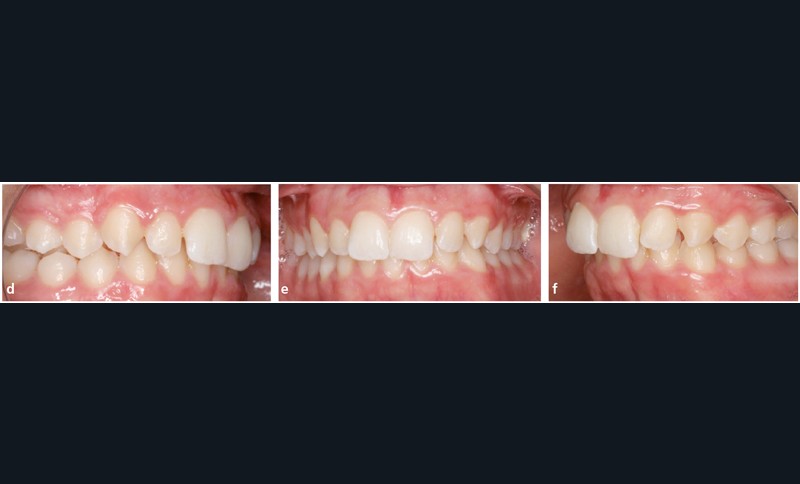

Analyse dentaire : les arcades dentaires sont asymétriques avec une Classe II molaire et canine mais plus importantes à gauche (fig. 1d, e et f).